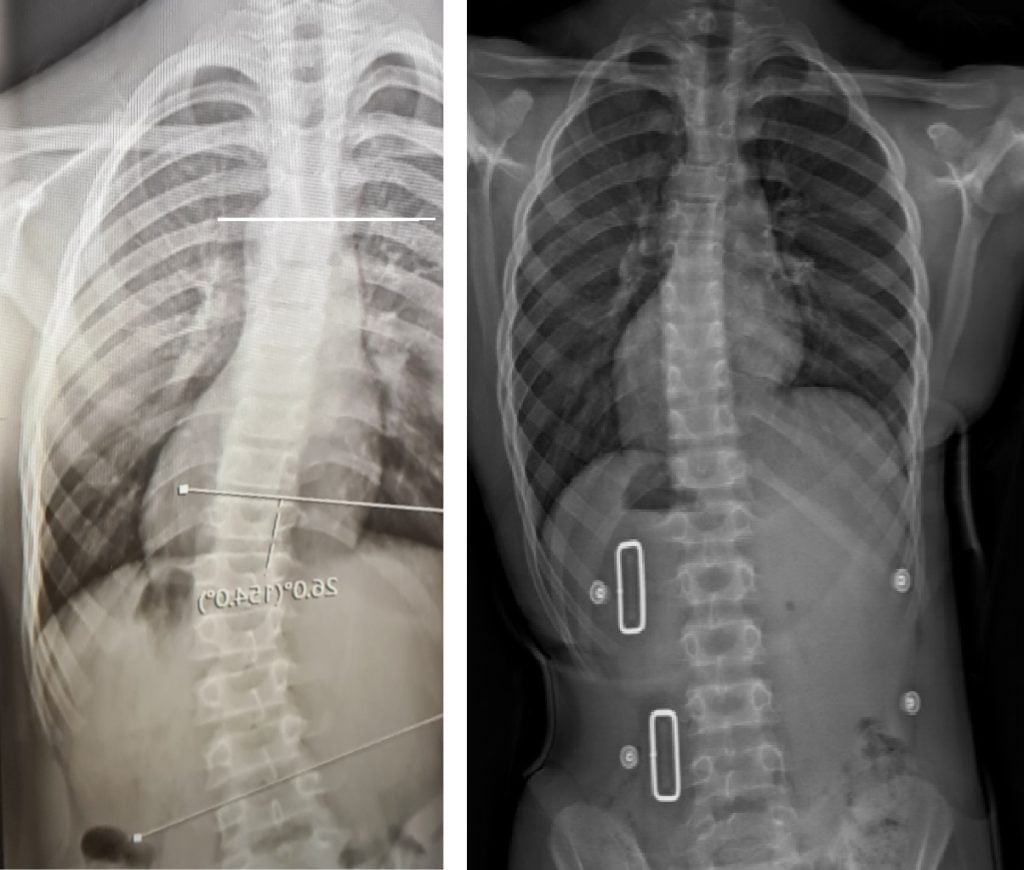

قبل و بعد

حتى أولئك الذين يعانون من اعوجاج العمود الفقري الشديد، حيث تزيد زاوية كوب عن 40 درجة، فقد استجابوا جيدًا لطريقه العلاج التي تعتمد على أحزمه الجنف تشينو-جينسينجن وبرنامج العلاج الطبيعي الذي يتبع مبادئ العلاج الطبيعي في شروث.

تم وصف زاوية كوب لأول مرة في عام 1948 من قبل الدكتور جون آر كوب، وهو جراح عظام أمريكي. تعتبر زاوية كوب التي تبلغ 10 درجات هي الحد الأدنى للزاوية لتحديد الجنف.